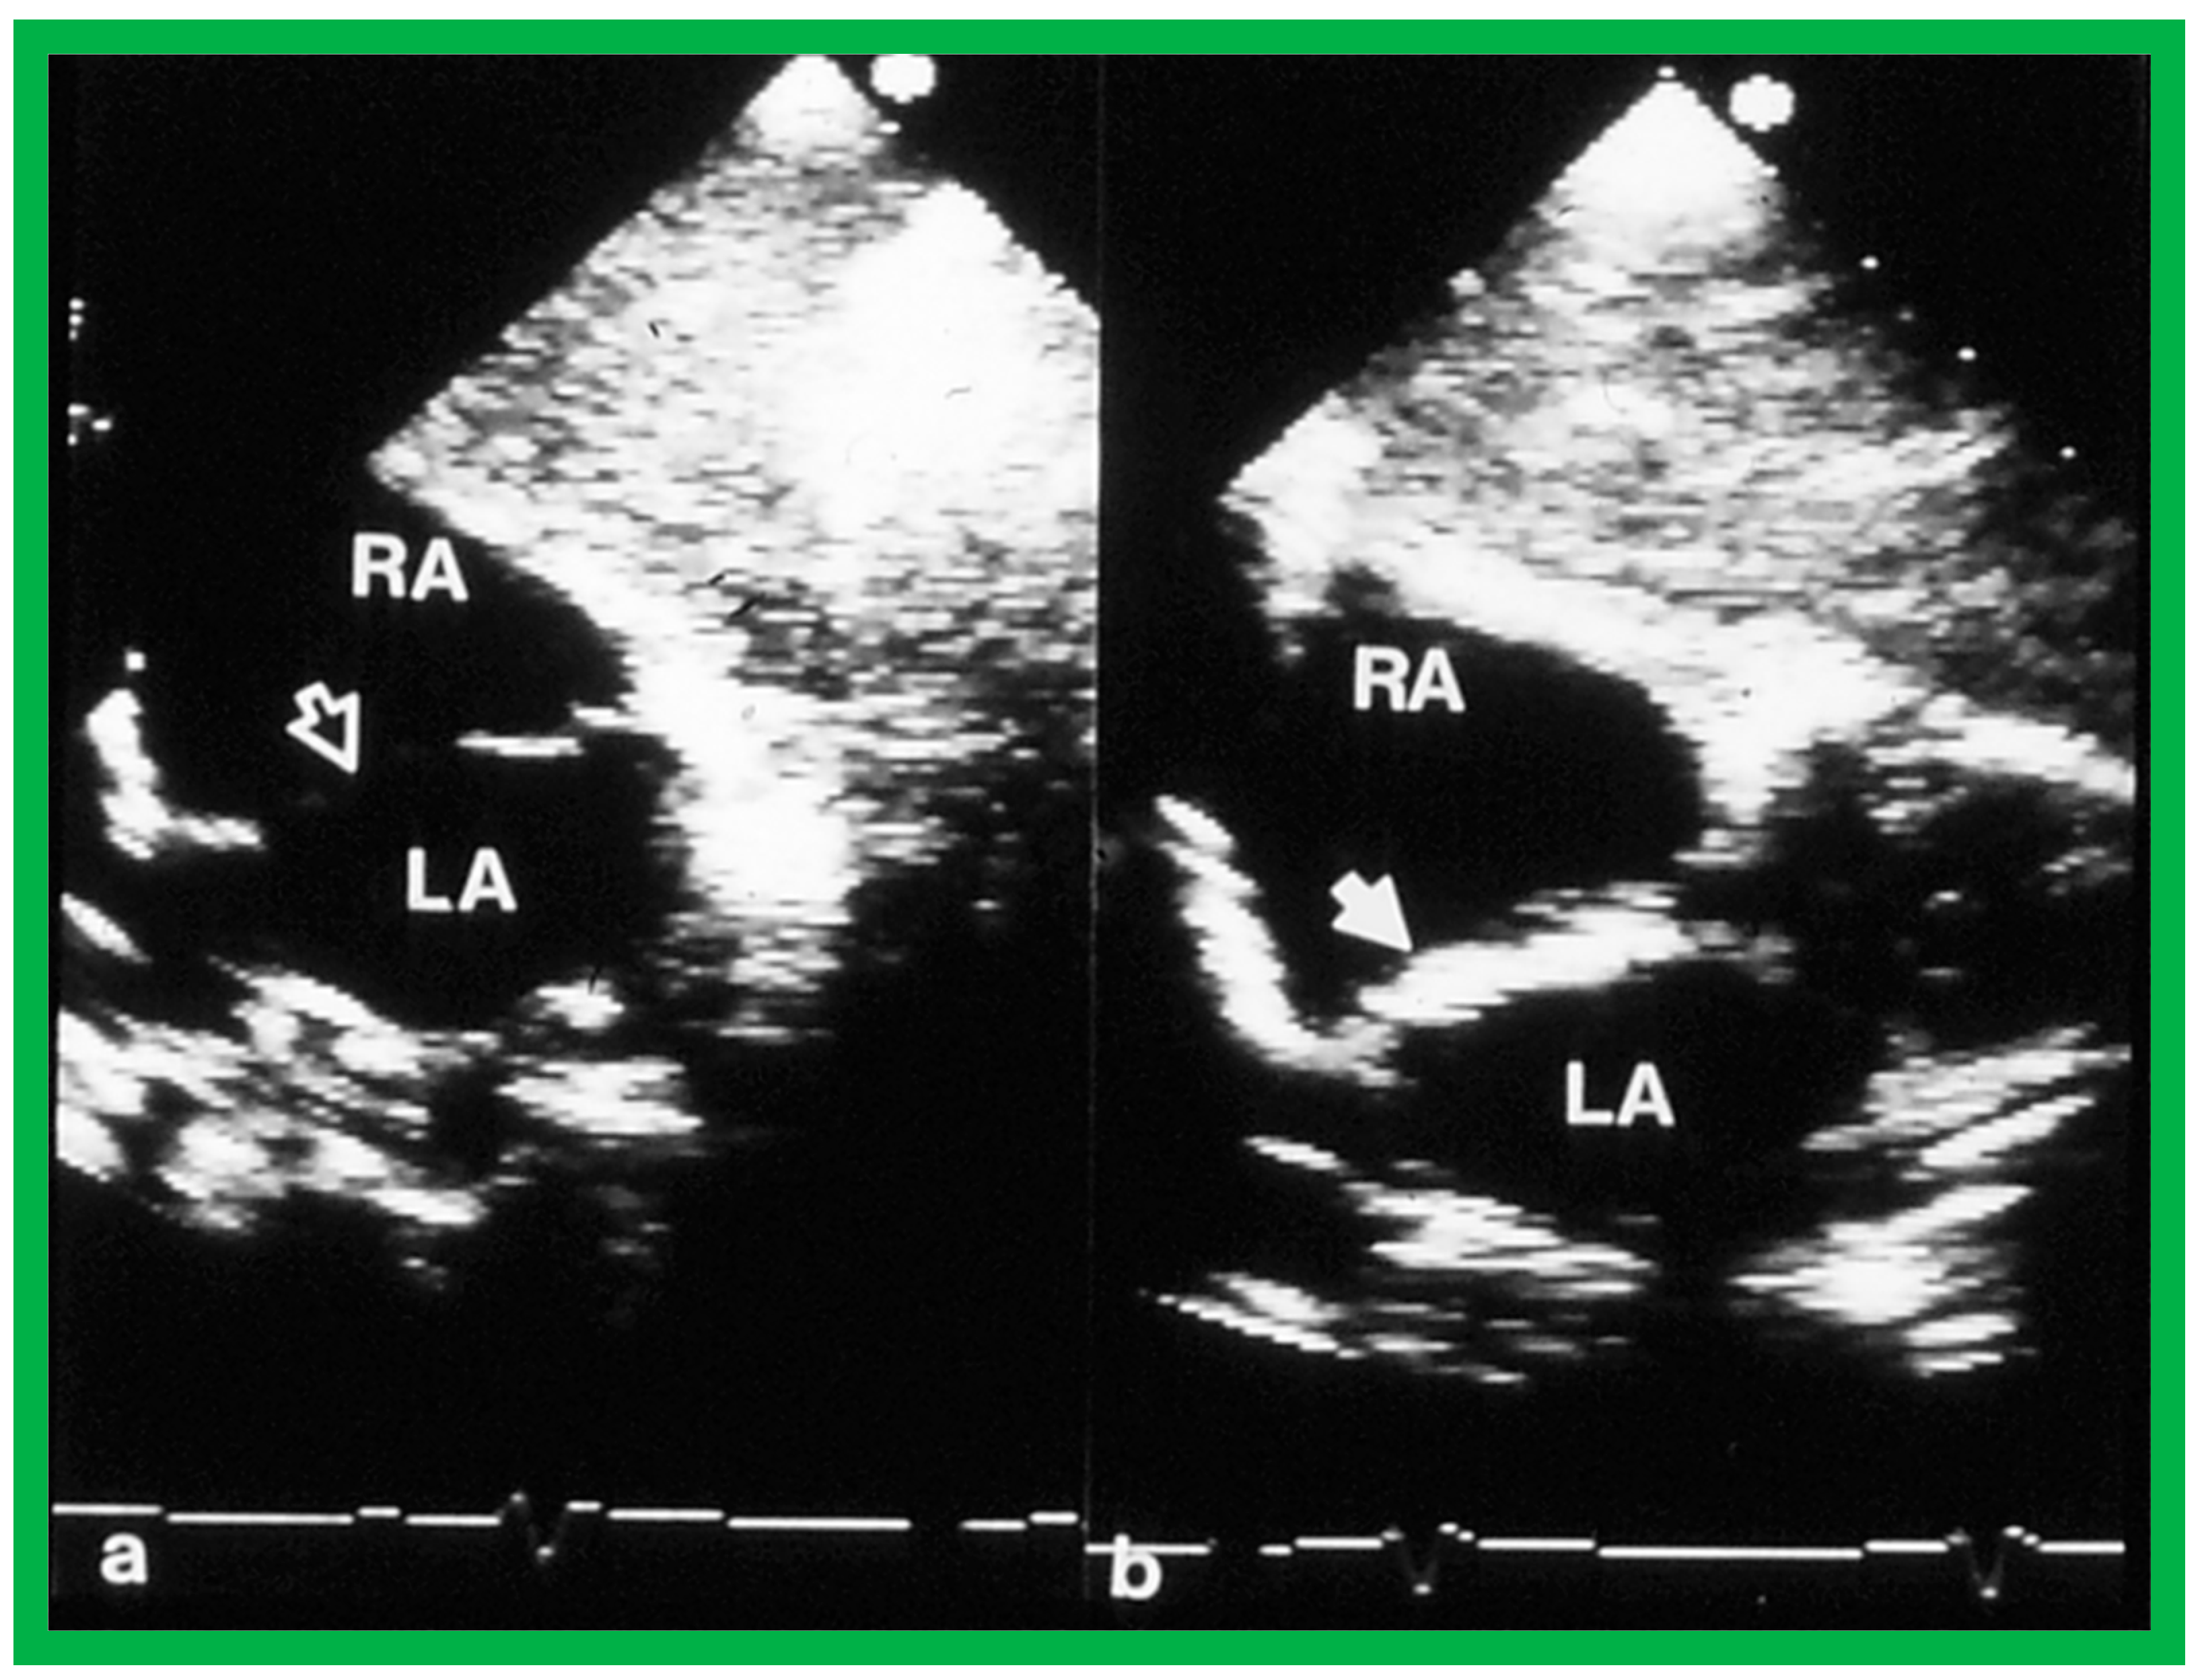

2. Diagnosis

- Hellenbrand, W.E.; Fahey, J.T.; McGowan, F.X.; Weltin, G.G.; Kleinman, C.S. Transesophageal echocardiographic guidance of transcatheter closure of atrial septal defect. Am. J. Cardiol. 1990, 66, 207–213. [Google Scholar] [CrossRef]

- Singh, G.K.; Marino, C.; Rao, P.S. Ultrasound as an adjunct to cardiac intervention in the pediatric patient. J. Invasive Cardiol. 1996, 8, 341–349. [Google Scholar] [PubMed]